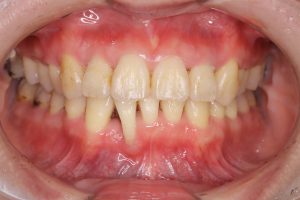

矯正医からの紹介で来院された30代の患者さんです。

10数年前に矯正治療を開始したものの、ブラケットやワイヤー等の矯正装置を装着したまま未来院になってしまったという経緯があり、現在は矯正治療は終了し、クリアリテーナーにて経過観察をしているということでした。

当院で、歯周病治療と舌側にある下顎前歯の抜歯をしてもらいたいということで紹介していただきました。

口腔内を確認すると、全体的に歯肉は炎症を起こして腫れており、下顎前歯の歯肉には著しい退縮を認めました。

歯周組織検査を行うと、30代にもかかわらず、中等度から重度の歯周ポケットを多数認めました。